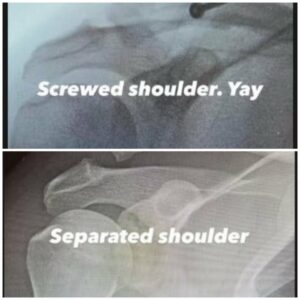

Актерот сподели и фотографии од неговите рендгенски снимки пред и по операцијата.

Во првата објава, Тејтум сподели рендгенска снимка од горниот дел од раката и рамото каде што јасно може да се види дека две коски се скршени.

– Одвоено рамо – напиша тој, а потоа следуваше втора фотографија после операцијата покрај која напиша: „Зашрафено рамо. Ура“.

За санирање на рамото на Тејтум бил употребен штраф, а ѕвездата го нарече искушението „тешко“ и „предизвик“.